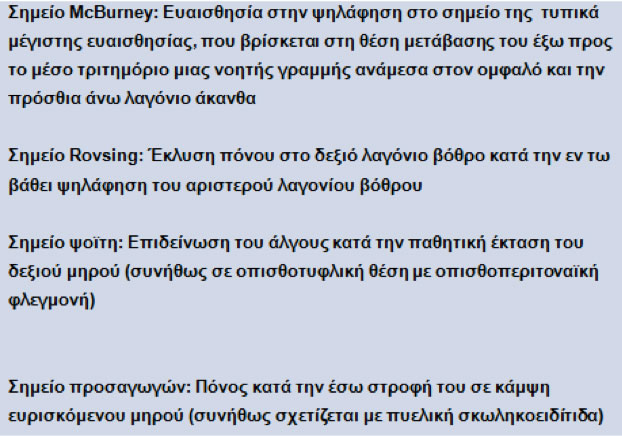

Τα ειδικά σημεία στην ψηλάφηση του ασθενούς με οξεία σκωληκοειδίτιδα συνοψίζονται στον Πίνακα 3.

Πίνακας 3.

Ειδικά σημεία στην οξεία σκωληκοειδίτιδα

Στη δακτυλική εξέταση: έντονη ευαισθησία στο πρόσθιο τοίχωμα του ορθού, αντίστοιχα με το Δουγλάσσειο χώρο, σε πυελική θέση της σκωληκοειδούς ή σε δημιουργία πυελικού αποστήματος.